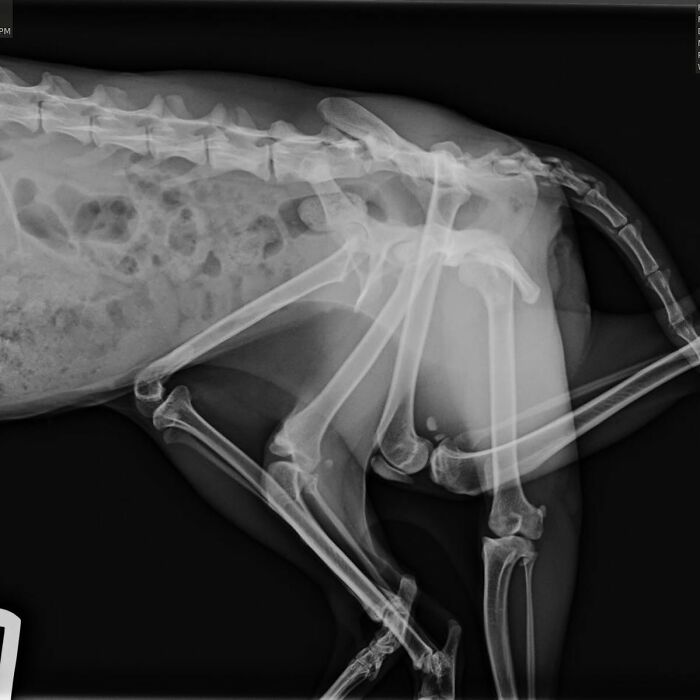

While in the womb, she absorbed a littermate, which caused her to have two extra legs and a second pelvis as she grew

At Windermere Veterinary Hospital, vets took X-rays and decided surgery was the best way to help Bitsy live more comfortably

Thanks to generous donors, Bitsy underwent a complex surgery to remove the extra limbs and pelvis